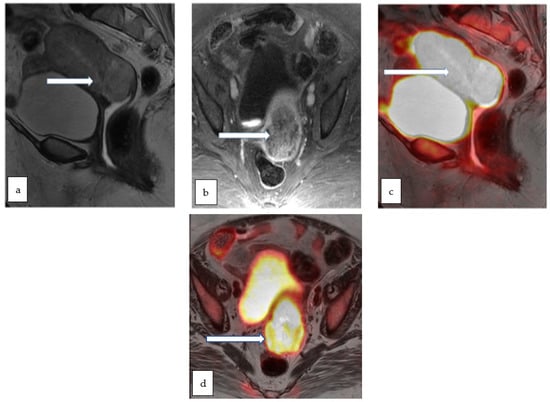

4.6. PET-MRI